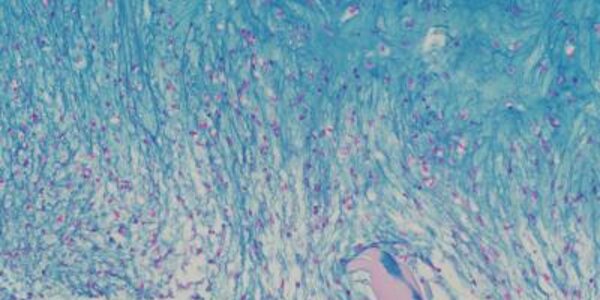

Bio-Engineers Grow Functional Human Cartilage In Vitro

Biomedical engineers at Columbia Engineering have successfully grown fully functional human cartilage in vitro from human stem cells derived from adult stem cells in bone marrow tissue.  Some researchers call cartilage the "official tissue of tissue engineering". Many groups have studied cartilage as an apparently simple tissue: one single cell type, no blood vessels or nerves, a tissue built for bearing loads while protecting bone ends in the joints. While there has been great success in engineering pieces of cartilage using young animal cells, no one has, until now, been able to…